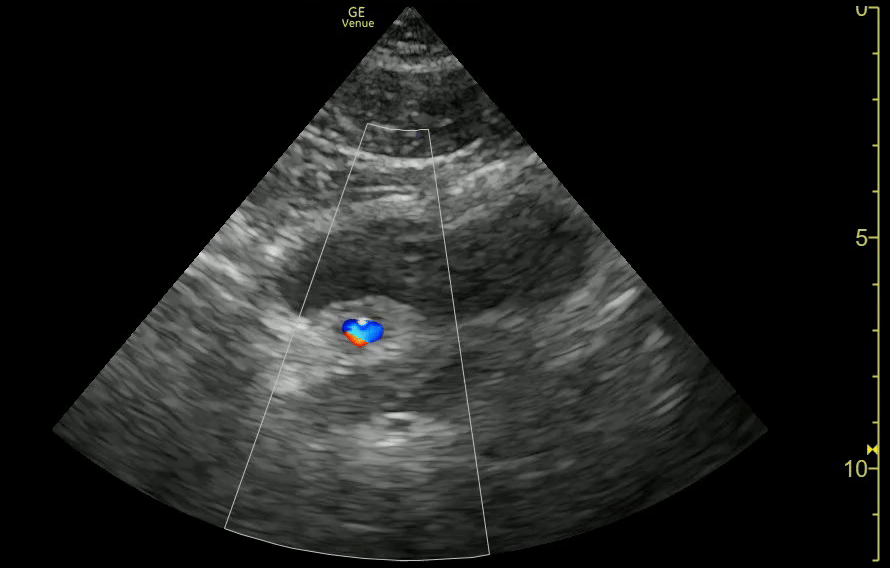

UVJ Stone with Left Hydro